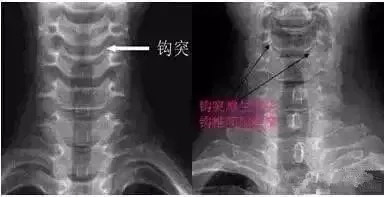

三钩突:钩突:正位片钩突呈三角形,钩椎关节宽约2mm;侧位片呈扇形,占椎体上缘后段的1/3~1/2;斜位片在椎间孔的前下方。钩椎关节退变在X片上表现为关节间隙变窄(小于2mm)和钩突的肥大、增生或尖刺状增生。

钩椎关节的重要毗邻:后方为脊髓、脊膜支和椎体的血管;后外侧部构成椎间孔的前壁,邻接颈神经根;外侧有椎动静脉和交感神经丛。

如1a图示C4/5间隙狭窄,椎体后缘增生后翘,1b图示C5/6,C6/7双侧钩椎关节增生,椎间孔变窄。